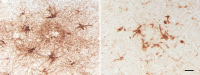

Figure 19

Reactive astrocytes (left; antibody to GFAP) and microglia (right; antibody to IBA1) in cortical Aβ plaques of two AD patients. Despite some overlap of the two cell types within plaques, astrocytic somata tend to be more peripherally located than are microglial somata. Bar = 20μm for both panels.